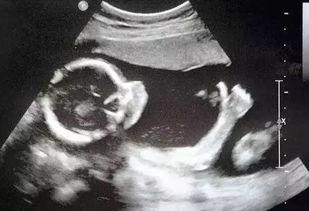

首先,让我们来一探究竟,这段视频到底展示了什么。据网友透露,这段视频记录了B超室里的一些日常场景,包括医生和护士的工作状态、孕妇的检查过程,以及一些温馨的瞬间。从视频中可以看出,B超室的工作环境相对封闭,但医护人员的工作态度却非常认真负责。

视频一经曝光,立刻引发了网友们的热议。有人表示,这段视频让他们对B超室的工作有了更深入的了解,也让他们对医护人员充满了敬意。而有些人则对视频中的一些细节提出了质疑,比如医生在操作过程中是否过于严肃,孕妇在检查过程中是否感到不适等。